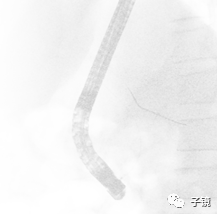

第一次插管进了胰管方向。

第二次进了胆管,造影发现胆总管中段和下段均有多发结石负影。